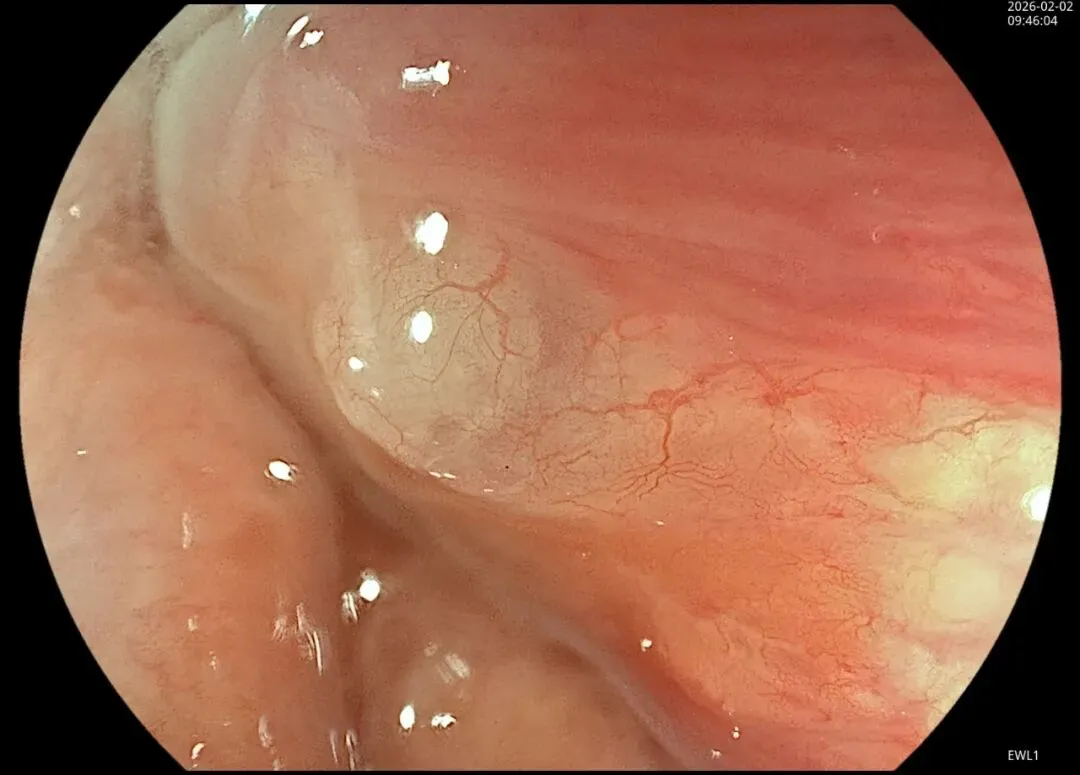

这一期不用码字,挺好的,很可惜一直没机会听过胡导讲的关于这个“花环征”的大课,学习内容来源于雨夜大师的号花环征:AIG背景的胃食管结合部的黄色颗粒状隆起及半透明“泡状”改变

补充自己在两例A型胃炎/AIG 观察到的“花环征”,巩固下学习效果。。。

case2:(made in china机子)👇

2.窄带光下可见颗粒状隆起呈褐色改变,放大可见细微网状血管结构及半透明“泡状”改变

进镜至贲门观察到“花环征”,提示存在AIG的可能,带学生的内镜老师这个moment可以装一把,不过。。。偶尔也有翻车的时候,以下这例是在“Hp现症感染C3萎缩”患者的花环

有待进一步研究。。。